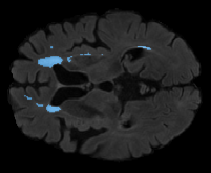

We evaluated our method in segmenting WMH from T1-w images using: a) Synthesized FLAIR images by treating the synthesis as a preprocessing step – we will refer to this method as offline synthesis; b) Synthesized FLAIR images using the proposed method, and c) without any synthesis – we will refer to this method as Unimodal. Baseline methods are illustrated in Figure 2

Table 2: Segmentation results for all proposed methods, each column represent a different slide in the image, blue areas are regions which were correctly labeled, false positives are shown in green, and false negatives in yellow

In order to better understand the above results, we visually analyzed the output segmentation performed for each method. Table 2 shows the results for three different slices (one slice per column). As illustrated, the proposed method is able to produce less false positives. It is also important to note that, unimodal segmentation is the one that produces more false positives, showing the advantage of using synthetic data. Regarding the nature of false positives, it can be easy to see in the third column a large number of false positives are on the border of periventricular lesions for the Unimodal method in comparison to the proposed method. Also from the first and second column, it can be observed that Unimodal tend to produce more small regions of false positives near to cortical areas. Removing such false positives requires additional post-processing steps, therefore, it is of value avoid this kind of over-segmentation. It can also be noted that synthesis methods tend to produce the same kind of false negatives, this may be due to the blurring effects in synthesized images since the information available during testing is limited – which otherwise is available from a FLAIR sequence.